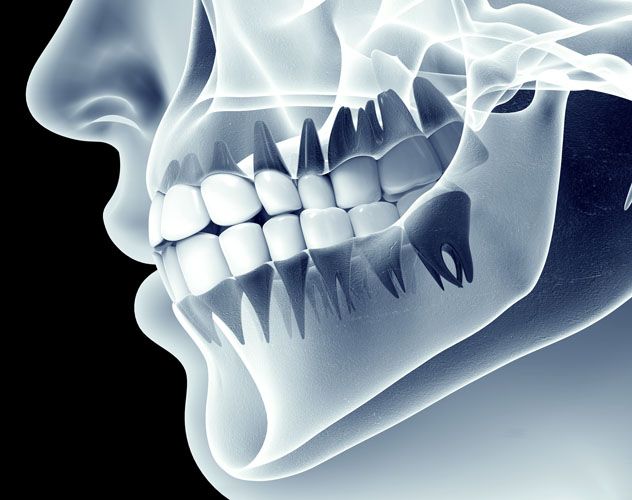

Over the past 10 years, the popularity of Dental Implants has absolutely taken off.  There are many reasons for this, however, I believe the main reason lies in their versatility and predictability.Dental implants are titanium tooth replacements which are placed into the jaw.  They are very similar in shape and size to the actual tooth roots they replace.  The procedure to place them is surprisingly comfortable, with the use of only local anesthesia, and very often the whole procedure takes about as long as a typical filling.  The advent of  Dental CAT...

CT Scans Improve Dental Implant Surgery

Advancements in dental technologies have allowed dentists to improve the delivery of Dental Implants to their patients.  The use of dental CT scans have allowed more accurate, and safe placement of dental implants, while minimizing the surgical time. For decades, the CT scan has been used in medicine to evaluate the condition of bony structures throughout the body.  Much like an MRI, it captures a 3-Dimensional view of the desired area.  The major difference is that the CT scan is an x-ray exam.  It is meant to diagnose the health, quality, and...